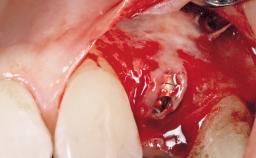

A 42-year-old female patient was referred to our clinic at the School of Dentistry of the University of São Paulo in November 2004, presenting a deficient restoration in the upper left central incisor. The clinical examination revealed no gingival retraction or any signs of gingival inflammation and, therefore, previous periodontal treatment was not considered. The patient presented a high lip line at full smile and a thin tissue biotype. This combination characterized a high-risk situation from an anatomic point of view, which required careful preoperative planning and cautious surgical execution.

Placement Protocol Immediate implant placement

Tooth Site Maxillary incisor or canine

Socket Morphology Single-root socket

Socket Integrity Sufficient, with intact bone walls

Bone Volume Sufficient, with intact walls